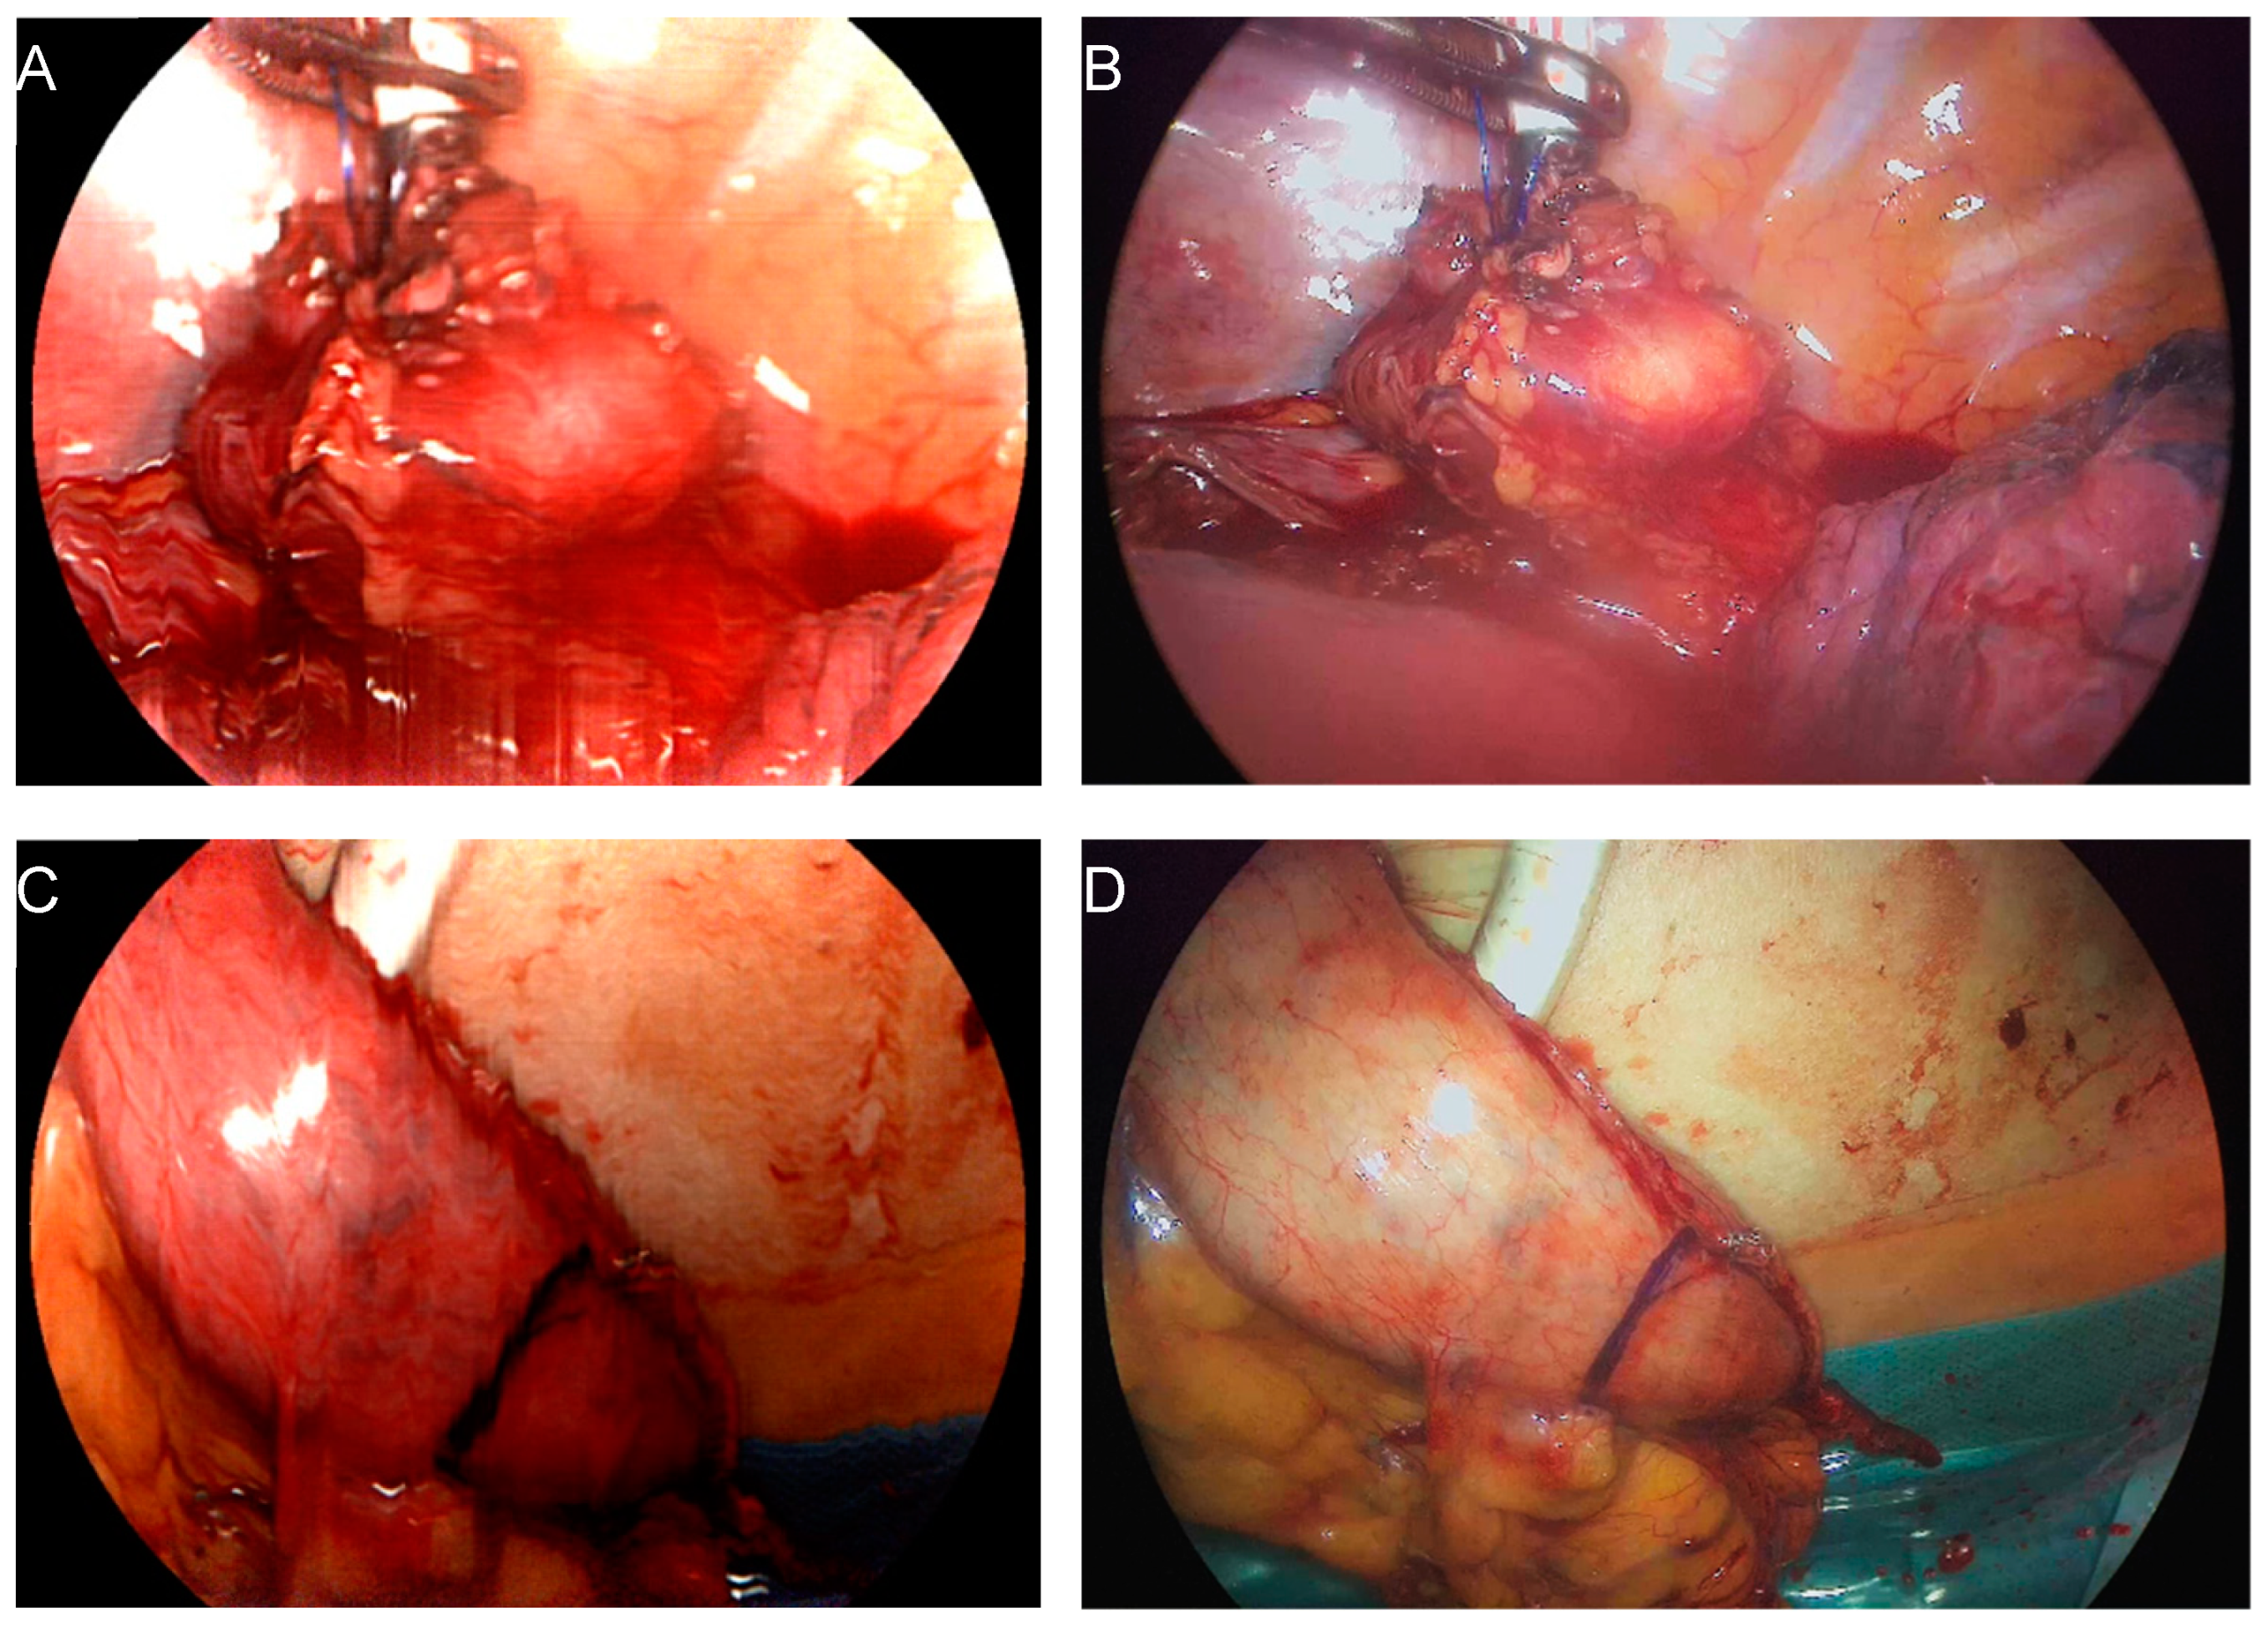

2.2. Surgical Procedure and Hyperspectral Imaging

- Thomaßen, M.T.; Köhler, H.; Pfahl, A.; Stelzner, S.; Mehdorn, M.; Thieme, R.; Jansen-Winkeln, B.; Gockel, I.; Chalopin, C.; Moulla, Y. In vivo evaluation of a hyperspectral imaging system for minimally invasive surgery (HSI-MIS). Surg. Endosc. 2023, 37, 3691–3700. [Google Scholar] [CrossRef] [PubMed]